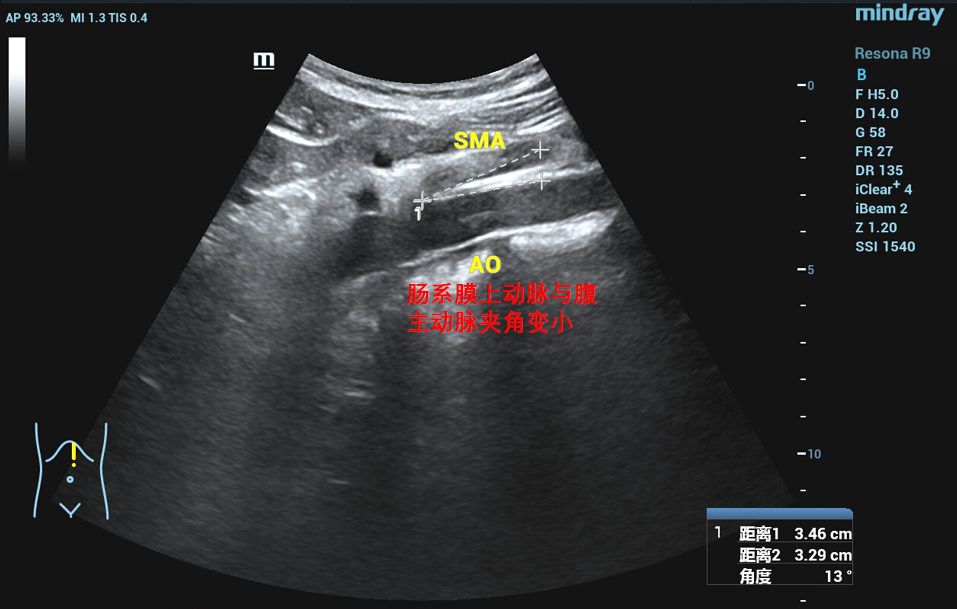

胡桃夹综合征,也称胡桃夹现象。是指左肾静脉回注下腔静脉过程中,需穿经由腹主动脉和肠系膜上动脉形成的夹角内受到挤压而引起的血尿、蛋白尿和左腰腹疼痛等临床症状。又称为左肾静脉受压综合征。近年来随着诊疗技术的发展。胡桃夹综合征引起的血尿发病率呈逐渐上升趋势,越来越受到临床的关注。

正常情况下,腹主动脉与肠系膜上动脉所形成的夹角为45度到60度,并为脂肪、淋巴、纤维结缔组织等填充,而左肾静脉并不受压。因为某些情况下可使夹角变窄,左肾静脉受压,导致左肾瘀血、肿大,以及左生殖腺静脉瘀血、曲张。

在泌尿外科三病区柯昌兴主任、杨博伟副主任医师、李宇航博士团队的精心准备和密切配合下,顺利为患者完成“腹腔镜(3D)下左肾静脉外支架置入术”。术中,见左肾有3根动脉,其中一根动脉绕行并压迫左肾静脉(术前阅片已确认),左肾静脉入肠系膜上动脉与腹主动脉夹角处,其周围纤维条索较多,此处左肾静脉明显变窄,离断纤维条索后此处左肾静脉明显增宽,充分游离左肾静脉近端至下腔静脉,远端至“其中一根动脉绕行并压迫左肾静脉”处,离断左性腺静脉和肾上腺中央静脉。柯昌兴主任团队成功放置一根6cm长带外支撑环的人工血管固定在患者左肾静脉外面,为受压的左肾静脉支撑起一条“生命通道”,提供持久的支撑力对抗肠系膜上动脉和腹主动脉的压迫。整个手术非常顺利,耗时约3小时,出血约10毫升。术后3天,患者康复出院,且腰痛、血尿等术前临床症状明显缓解,手术效果非常显著。